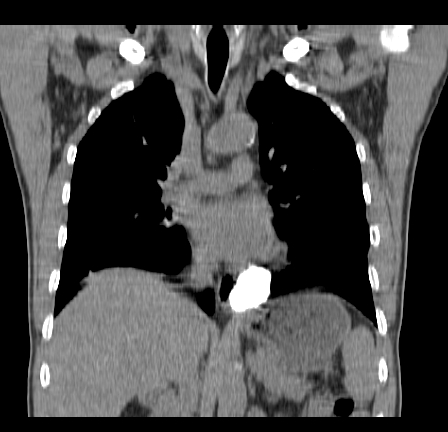

以下是引用影像孺子牛在2009-5-20 23:18:00的发言:[br]左侧后心膈角处类椭圆形钙化灶,最常见的是淋巴结钙化,但太大了不支持,其它如食管囊肿钙化、实性畸胆瘤等。何东西钙化真不好定。

以下是引用zbp537在2009-5-20 20:52:00的发言:[br]钙化灶,来源不好说。